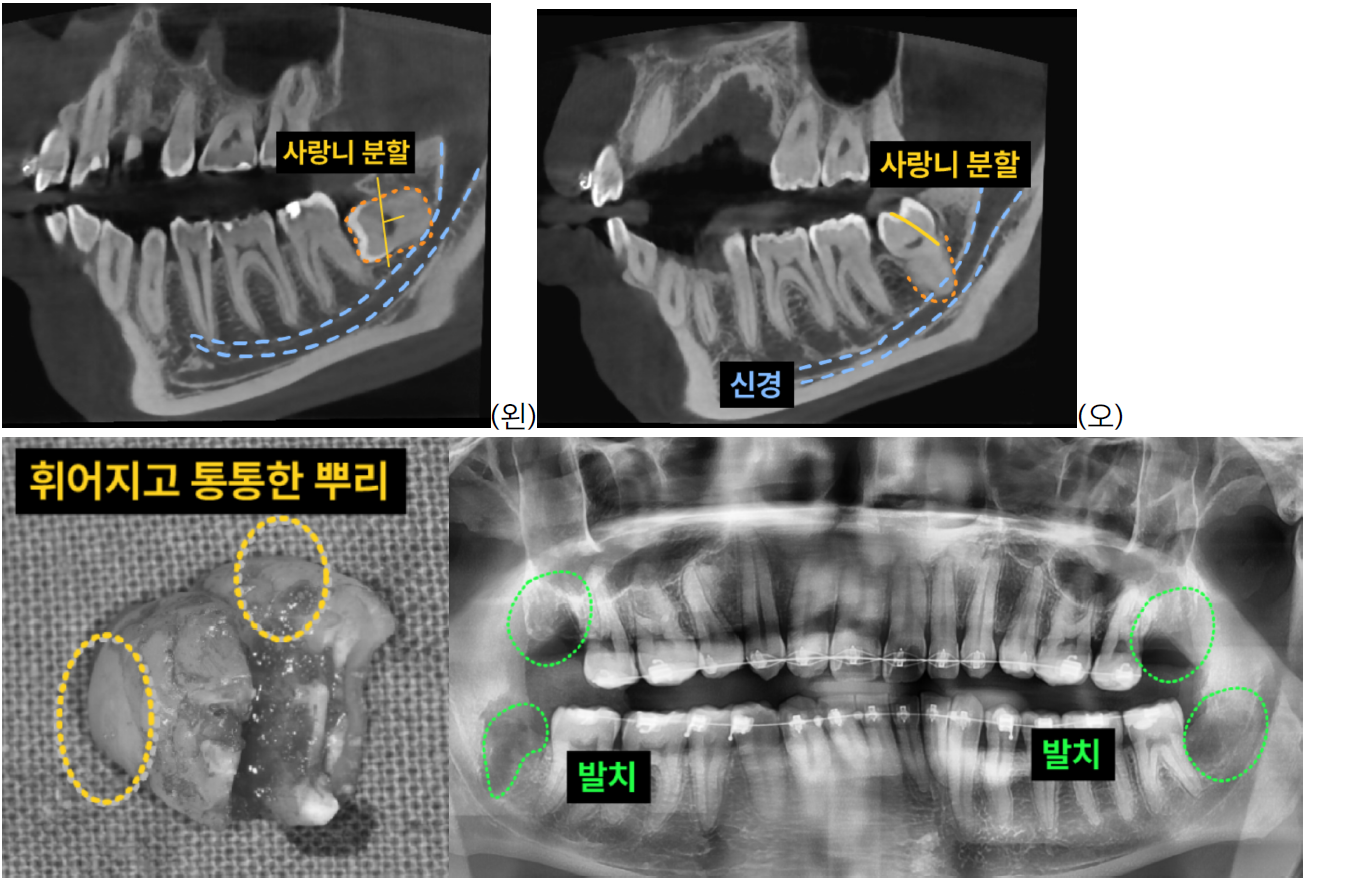

| "동네 치과에서는 어렵다던 사랑니", "대학병원으로 가야 한다던 사랑니" 혹시 이런 이야기를 들어본 적 있으신가요? 사랑니 발치는 그 위치와 형태, 주변 신경과의 관계에 따라  고난이도 시술이 될 수 있습니다.  이백점치과는 어떤 형태의 사랑니든 정확하게 진단하고 안전하게 발치하여, 환자분들이 더 이상 고민하지 않도록 도와드립니다. CASE. 20대 남성 환자. 교정 치료를 위한 고난도 사랑니 발치 ○ 내원 동기: 교정 치료를 위해 상하좌우 4개의 사랑니 발치를 의뢰받아 내원하셨습니다. ○ 진단: - 3D CT 촬영을 통해 사랑니의 정확한 위치와 매복 정도, 그리고 주변 신경관과의 관계를 면밀히 분석했습니다. - 왼쪽 아래 사랑니는 가로로 깊이 매복되어 신경과 매우 가까웠으며, - 오른쪽 아래 사랑니는 신경과 근접한 것은 물론 뿌리가 크고 통통하며 'ㄱ'자 형태로 휘어진 고난이도 형태였습 니다. ![]() 이백점치과의 정교한 사랑니 발치 과정 사랑니는 경우에 따라 하루에 모두 발치할 수도 있지만, 일반적으로 좌우를 나누어 진행합니다. 1. 세심한 발치 계획 수립: 3D CT 분석을 바탕으로 각 사랑니의 형태와 주변 구조물을 고려한 맞춤형 발치 계획을 수립합니다. 2. 정밀 분할 발치: 특히 깊이 매복되어 신경과 가까운 사랑니는 신경 손상 위험을 최소화하기 위해  사랑니의 머리(치관)와 뿌리(치근)를 적절히 분할하여 조심스럽게 발치합니다. 이 과정은 숙련된 의료진의 정교한 기술이 필수적입니다. 3. 성공적인 발치 완료: 좌우 상하 4개의 모든 매복 사랑니를 성공적으로 발치하여, 환자분은 불편함 없이 교정 치료를 위한 충분한 공간을 확보할 수 있었습니다. ![]() 안전하고 편안한 사랑니 발치, 이백점치과가 약속합니다 사랑니는 깊이 누워있거나 숨겨져 있다고 해서 무조건 발치해야 하는 것은 아니지만,  정과 같은 명확한 목적이 있을 경우에는 꼭 필요합니다. 이백점치과는 안전하고 편안한 발치를 최우선으로 합니다. - 통증 최소화: 숙련된 마취와 섬세한 시술로 통증을 최소화합니다. - 불안감 해소: 치과 치료에 대한 두려움이 있는 환자분들을 위해 수면치료(수면 마취)를 동반한 발치도 가능하여, 편안하게 시술받으실 수 있습니다. 이제 사랑니 때문에 더 이상 고민하지 마세요! 이백점치과에서 정밀 진단과 숙련된 노하우로 여러분의 사랑니를 안전하고 편안하게 해결해 드리겠습니다.  |